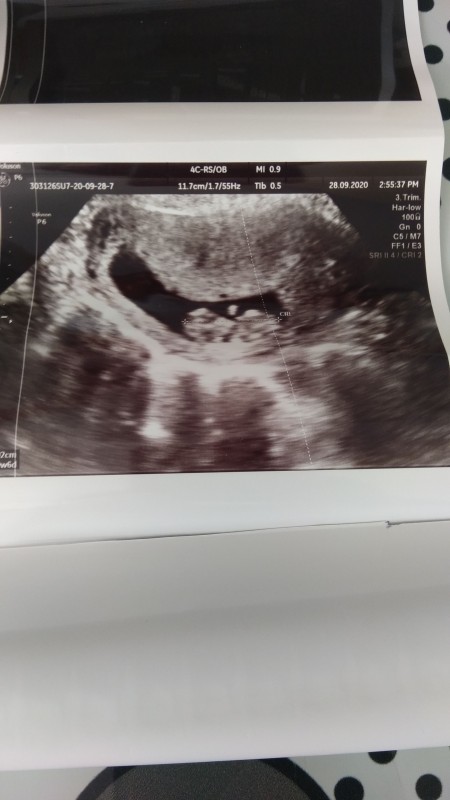

10 Haftalik Gebelik Hamilelik Goruntusu